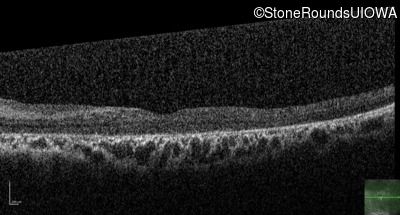

Optical Coherence Tomography - Left - 10/125

Exemplar / OCT Stack